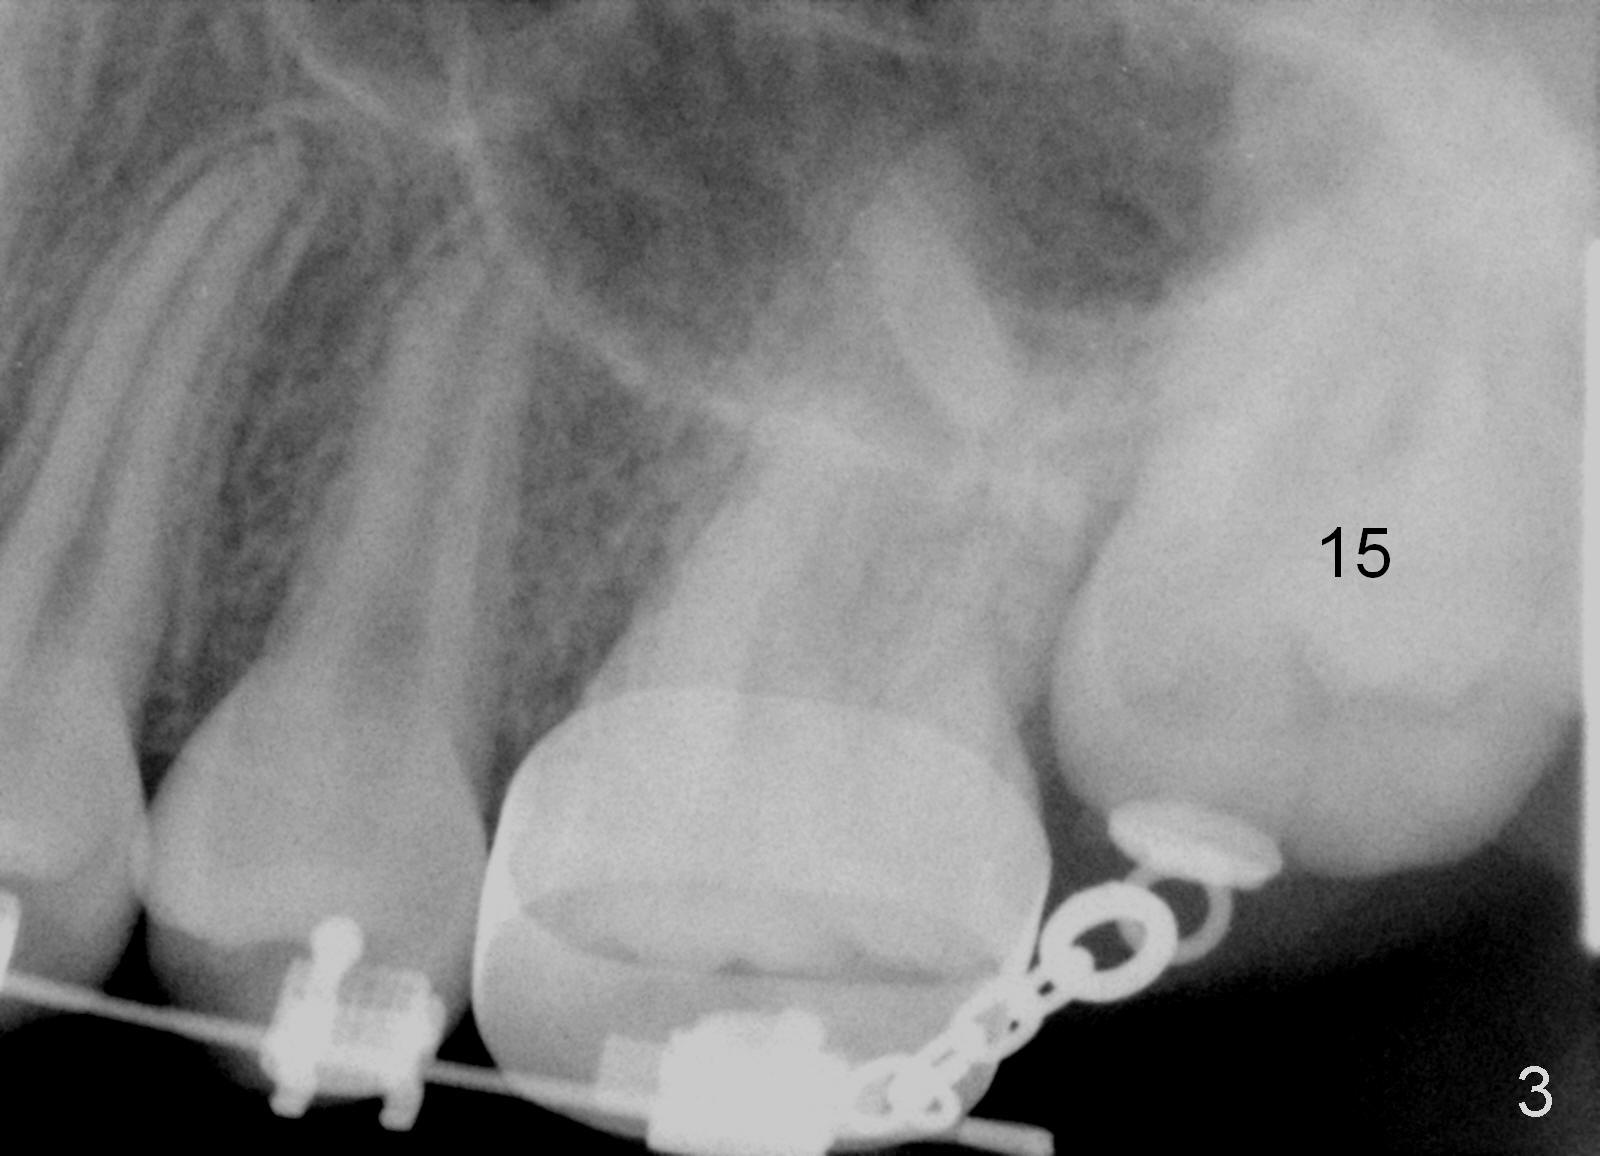

When the female patient was 11 years 2 months (Fig.1) and 12 years 10 months (Fig.2) old, the eruption of #15 is delayed. The tooth is surgically uncovered with bonding an eruption chain 1 month post banding. Three (Fig.3), 4 (Fig.4) and 6 (Fig.5) months post banding, eruption appears to be slow with elastics.

The distobuccal cusp of the tooth is subgingival 8 months post banding (Fig.6 (mirror view) *). A 2nd surgery is performed to expose the gold chain (Fig.7 <) and a bracket is placed. With arch wires, eruption of the impacted tooth is quickened (Fig.8). Later a 3rd minor surgery is done to place a lingual button to facilitate lingual cusp eruption. Finally a band has to be placed at #15. Treatment finishes in 2 years. The patient (15 years 2 months old) returns for follow up 3 months post debanding (Fig.9). There is no bone loss around the tooth #15 2 years 4 months post de-banding (Fig.11, as compared to the tooth #2 (Fig.10)).